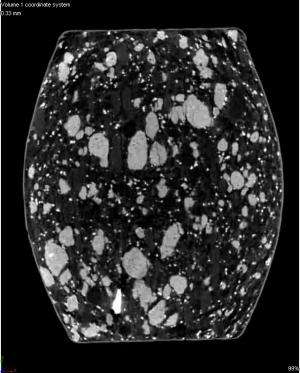

Physical and chemical properties